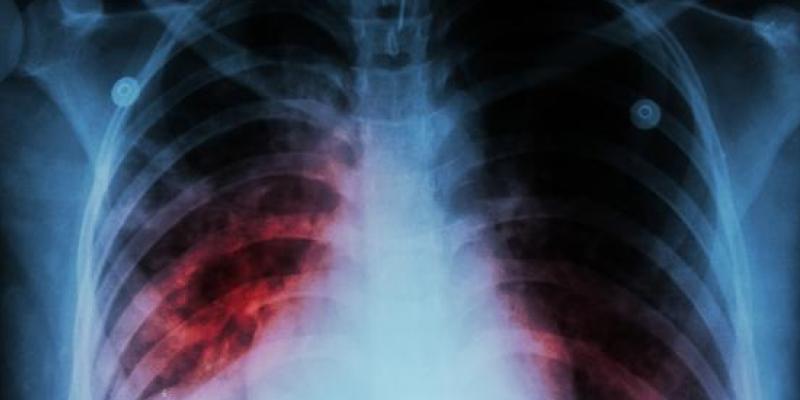

Radiografía de unos pulmones con tuberculosis

La tuberculosis es una enfermedad causada por Mycobacterium tuberculosis, una bacteria que casi siempre afecta a los pulmones. Es curable y prevenible.